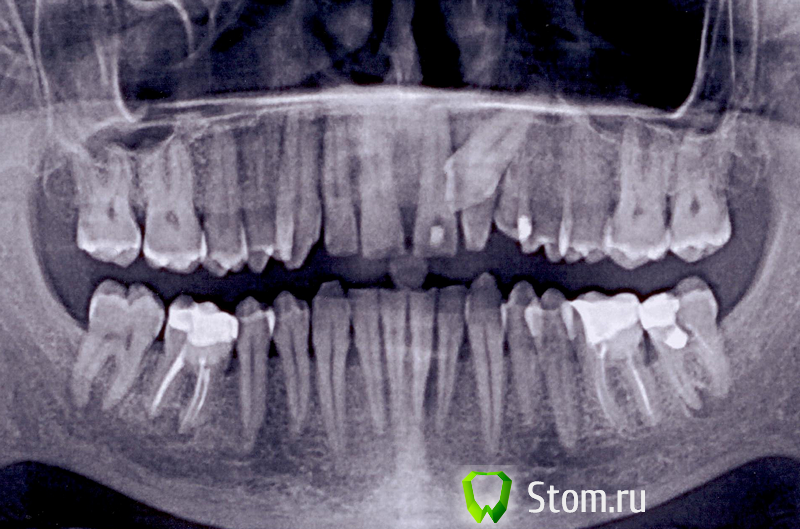

Мармышка Опубликовано 21 января, 2012 Поделиться Опубликовано 21 января, 2012 В общем, вот такая ситуация. Человек жил с этим 33 года и не подозревал о такой лежачей красоте) 30 декабря начал болеть 21 зуб, при т ом жалобы, как при периодонтите, очень болел при дотрагивании и даже уже начала отекать переходная складка. Зуб интактный, сделали снимок, на 100 процентов была уверена, что периодинти и всё дело в нём. Думала, открыть помыть, кальций временно, снять острые явления, довести лечение 21 до конца, а уж потом разбираться с ретенированной тройкой. Но оказалось, что 21 живой зуб!!! в общем, пришлось временно запломбировать, чтобы сделать панорамник (к сожалению, у нас делают панорамники в другой клинике и по предварительной записи). В общем, после консультации с хирургом пришли к выводу, что тройка начала упираться в 21, и надо её убирать. 21 залечила под анестезией. Потом выложу фото. Но там такая деструкция кости...((((Самое печальное, что ситуация эта у очень близкого мне человека... закон подлости..были ли у вас такие ситуации? очень страшно, что 21 зуб полетит во время операции. Во вторник поедем на 3В диагностику, хочется посмотреть с какой стороны тройка сидит и на каком расстоянии к соседним зубам. Ссылка на комментарий

kriokov Опубликовано 21 января, 2012 Поделиться Опубликовано 21 января, 2012 +1 за вестибулопозицию клыка. Прежде чем удалять посоветуйтесь с ортодонтом. думаю вытянуть будет вернеза небное положение, по анализу ОПТГ. Размеры коронки ретенированного клыка увеличены в размере и растянуты, а корень нет, значит обьект (коронка) близко к фокусу- т.е небно Ссылка на комментарий

DmitrySH Опубликовано 21 января, 2012 Поделиться Опубликовано 21 января, 2012 Эндо 21 зуба зачем? Офф топ. Если человек близкий пора бы 37 и 46 заняться. А то дождетесь.. Ссылка на комментарий

Мармышка Опубликовано 21 января, 2012 Автор Поделиться Опубликовано 21 января, 2012 до знакомства со мной человек лечился в другой клинике и полнрстью доверял врачу, и даже когда возникла проблема решил идти туда же, я уговорила к себе. После ОПТГ я посмотрела на нижние зубы и поняла, что никуда он кроме сменя не пойдёт!!! была немного в шоке (хотя "немного" это слабо сказано... хрен знает, что ему там делали, карточку теперь не допроситься). О нижних буду думать потом, теперь нужно разобраться с тем, что болит. Эндо сделано по 2 причинам: 1- раскрывала этот зуб изначально моя коллега, я в отпуске была как раз в этот день и не могла выйти на работу, 2- хирург считает, что при операции он может повредиться, да и по снимку большая деструкция, явно тройка к единице прилегает или киста такая уже. Разве нет? периодонтальная щель не прослеживается(( Ссылка на комментарий

juli63 Опубликовано 22 января, 2012 Поделиться Опубликовано 22 января, 2012 После ОПТГ я посмотрела на нижние зубы и была немного в шоке (хотя "немного" это слабо сказано... ). но особенно интересно, что делали с 37 . потом расскажите, что там. может это новое веяние в стоматологии-"тунельная эндодонтия" Ссылка на комментарий